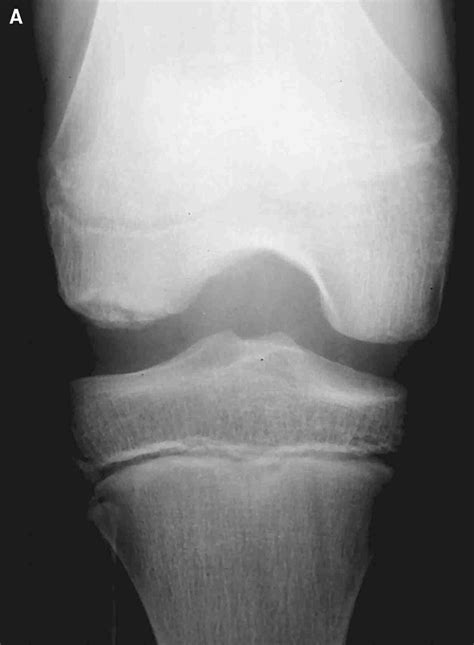

Osteochondral lesion of talar dome - Riverside Podiatry